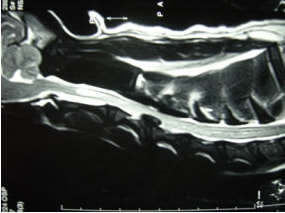

〈MRI検査:胸腰部椎間板ヘルニア〉

〈MRI検査:胸腰部椎間板ヘルニア2〉

突然ギャンと鳴き両後肢麻痺したとのことで来院されました。触診にて腰部の圧痛を認めました。尿失禁が認められ、深部痛覚は消失していました。聴診上での異常はみられず、後肢の股圧は触知可能でした。血液検査、胸腰椎のレントゲン検査では異常を認めませんでした。MRI検査の結果、第3腰椎領域にてT1強調画像で等信号、T2強調画像で等〜やや高信号、造影剤にて均一に増強される脊髄を腹側から圧迫する腫瘤性病変を認めました。

■ MRI検査

第5-6腰椎間で右側神経根が腫大し、脊柱管内に連続した腫瘤病変が認められました。脊髄および馬尾神経は右側から重度に圧迫されていました。